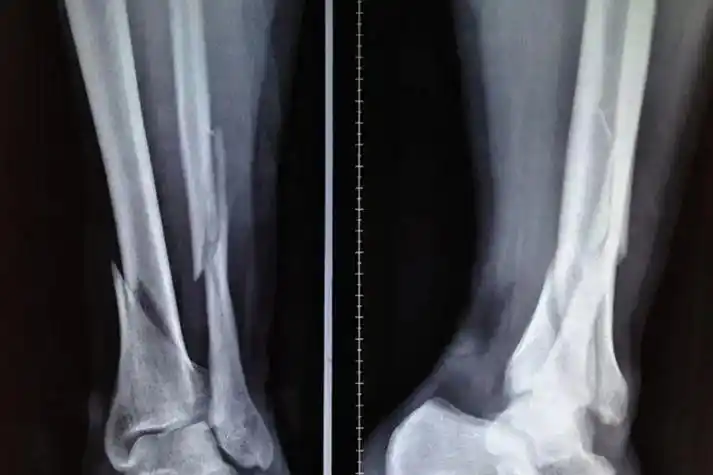

市二院骨科成功应用mippo技术治疗小腿粉碎性骨折

术前x光片

关于小腿骨科的问题x片!